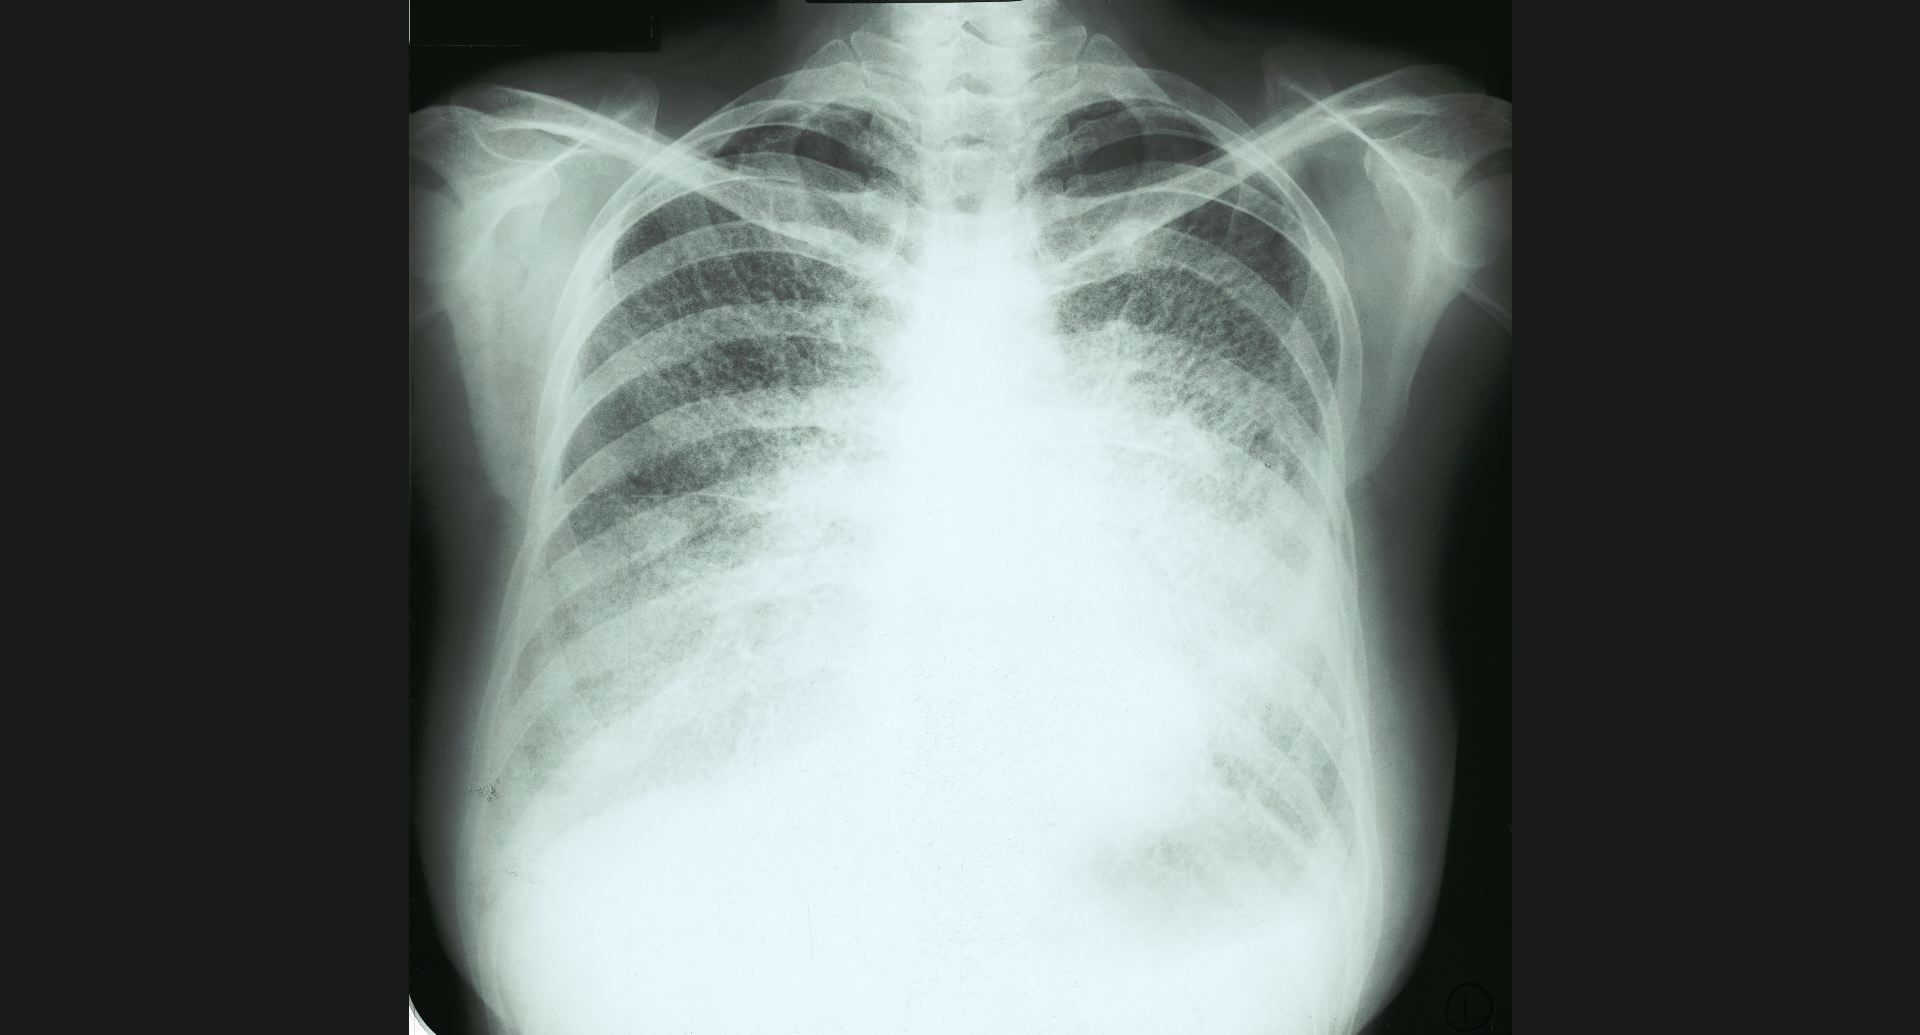

fig.6(97KB) :Alveolar proteinosis (tomography)

butterfly pattern, air bronchogram。